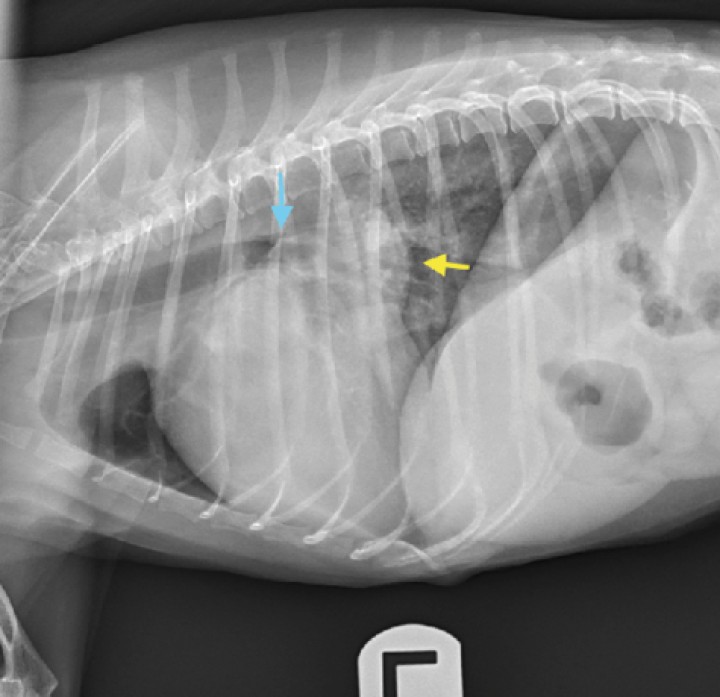

<p>Radiografía lateral izquierda de un perro con cardiomegalia (VHS = 12,5 CV) y dilatación de atrio izquierdo. Se observa un aumento de opacidad de tejido blando entre las 12 y las 2 de la silueta cardiaca, según la cronología del reloj, compatible con un aumento del tamaño del atrio izquierdo (flecha amarilla). Se observa además el desplazamiento dorsal de la tráquea, así como la compresión del bronquio principal izquierdo (flecha azul). VHS: <em>Vertebral Heart Score</em>; CV: cuerpos vertebrales.</p>

Figura 2

Radiografía lateral izquierda de un perro con cardiomegalia (VHS = 12,5 CV) y dilatación de atrio izquierdo. Se observa un aumento de opacidad de tejido blando entre las 12 y las 2 de la silueta cardiaca, según la cronología del reloj, compatible con un aumento del tamaño del atrio izquierdo (flecha amarilla). Se observa además el desplazamiento dorsal de la tráquea, así como la compresión del bronquio principal izquierdo (flecha azul). VHS: Vertebral Heart Score; CV: cuerpos vertebrales.

Se trata de la enfermedad cardiaca más frecuente en el paciente canino, suponiendo aproximadamente un 75 % de las cardiopatías.[ Keene BW, Atkins CE, Bonagura JD, et al: ACVIM consensus guidelines for the diagnosis and treatment of myxomatous mitral valve disease in dogs. J Vet Intern Med 2019; 33: 1127-1140. [pubMed] ] Podemos hablar de ella como una enfermedad idiopática, hereditaria y degenerativa de la válvula atrioventricular izquierda que podría llevar a generar insuficiencia valvular (Figs. 2 y 3).